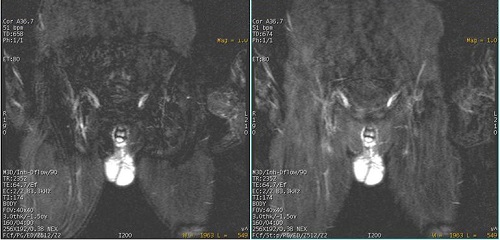

- For middle and upper stations, consider placing a posterior SAT pulse so that you can keep the slab size as small as possible for the optimum scan time. The SAT pulse is critical to reduce phase wrap when there is anatomy outside the FOV.

Figure 6. Exmaple of: Posterior SAT pulse positioned to minimize phase wrap

Figure 7. Left is pelvic image with no posterior SAT, right is image with posterior SAT pulse